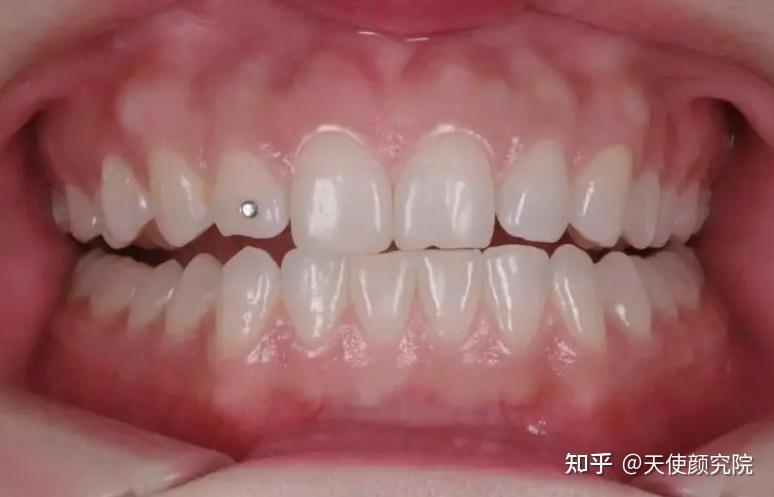

e、拥有正确规整的颌面:错误的牙齿排列还未严重影响骨骼肌肉前,及时矫治复原,可以有效引导脸型良性发育,拥有一个规整好看的颜面。

矫治前:牙齿凸,唇肌紧张

矫治后:牙、唇放松自然,颌面也规整